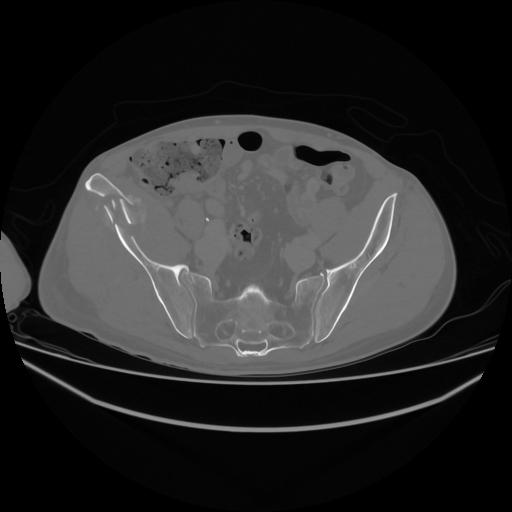

5 CUERPO,CE,Vol,1.0,CUERPO,,